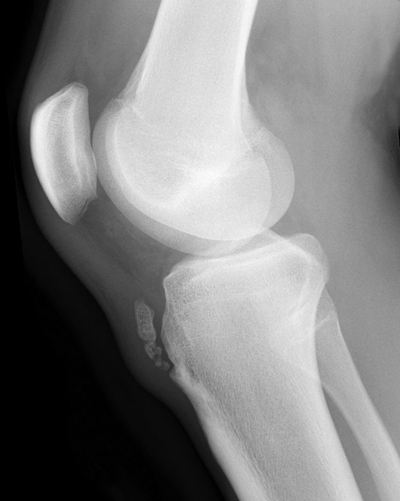

脛骨結節骨骺炎 (50)

脛骨結節骨骺炎 (6)

脛骨結節骨骺炎 (7)

脛骨結節骨骺炎 (8)

脛骨結節骨骺炎 (9)

脛骨結節骨骺炎 (43)

脛骨結節骨骺炎 (44)

脛骨結節骨骺炎 (45)

脛骨結節骨骺炎 (46)

脛骨結節骨骺炎 (47)

脛骨結節骨骺炎 (48)

脛骨結節骨骺炎 (49)

脛骨結節骨骺炎 (5)

脛骨結節骨骺炎 (41)

脛骨結節骨骺炎 (42)

脛骨結節骨骺炎 (37)

脛骨結節骨骺炎 (38)

脛骨結節骨骺炎 (39)

脛骨結節骨骺炎 (4)

脛骨結節骨骺炎 (40)

A:脛骨結節骨軟骨炎主要是由於劇烈運動時髕韌帶在脛骨結節附著處反覆牽拉引起的一種急性損傷或者撕脫,多發生青少年時期。主要表現為脛骨結節處明顯的腫脹、疼痛。特別是在跳高、跑步以及上下樓梯等活動時,疼痛感會明顯加重,經過休息可以得到緩解。曲膝時脛骨……

A:脛骨結節軟骨炎屬於無菌性的炎症,主要是脛骨結節部位,在腿部屈伸活動時,受到髕韌帶反覆的牽拉,就會在局部形成無菌性的炎性水腫的情況。在這種情況以後,一是避免蹲起,跑跳,上下樓梯的活動。再就是可以行脛骨結節部位的熱敷,來促進局部的血液循環,從而……